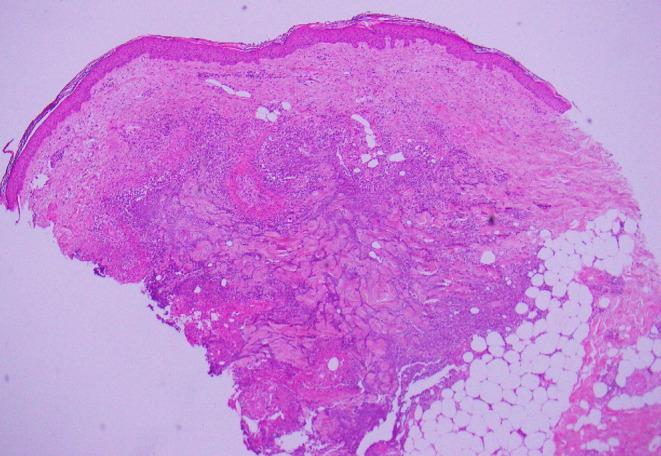

We describe the case of an 87-year-old woman who developed Sweet's syndrome with atypical mucosal involvement following a post-operative wound infection. The disease manifestations included two large, ulcerated plaques on both sides of the tongue as well as cutaneous lesions. Her lesions resolved promptly with oral prednisolone.

我们描述了一位87岁女性的病例,该患者在术后伤口感染后出现了伴有非典型黏膜受累的Sweet综合征。疾病表现包括舌两侧有两个大的溃疡斑块以及皮肤损害。她的病变通过口服泼尼松龙迅速消退。